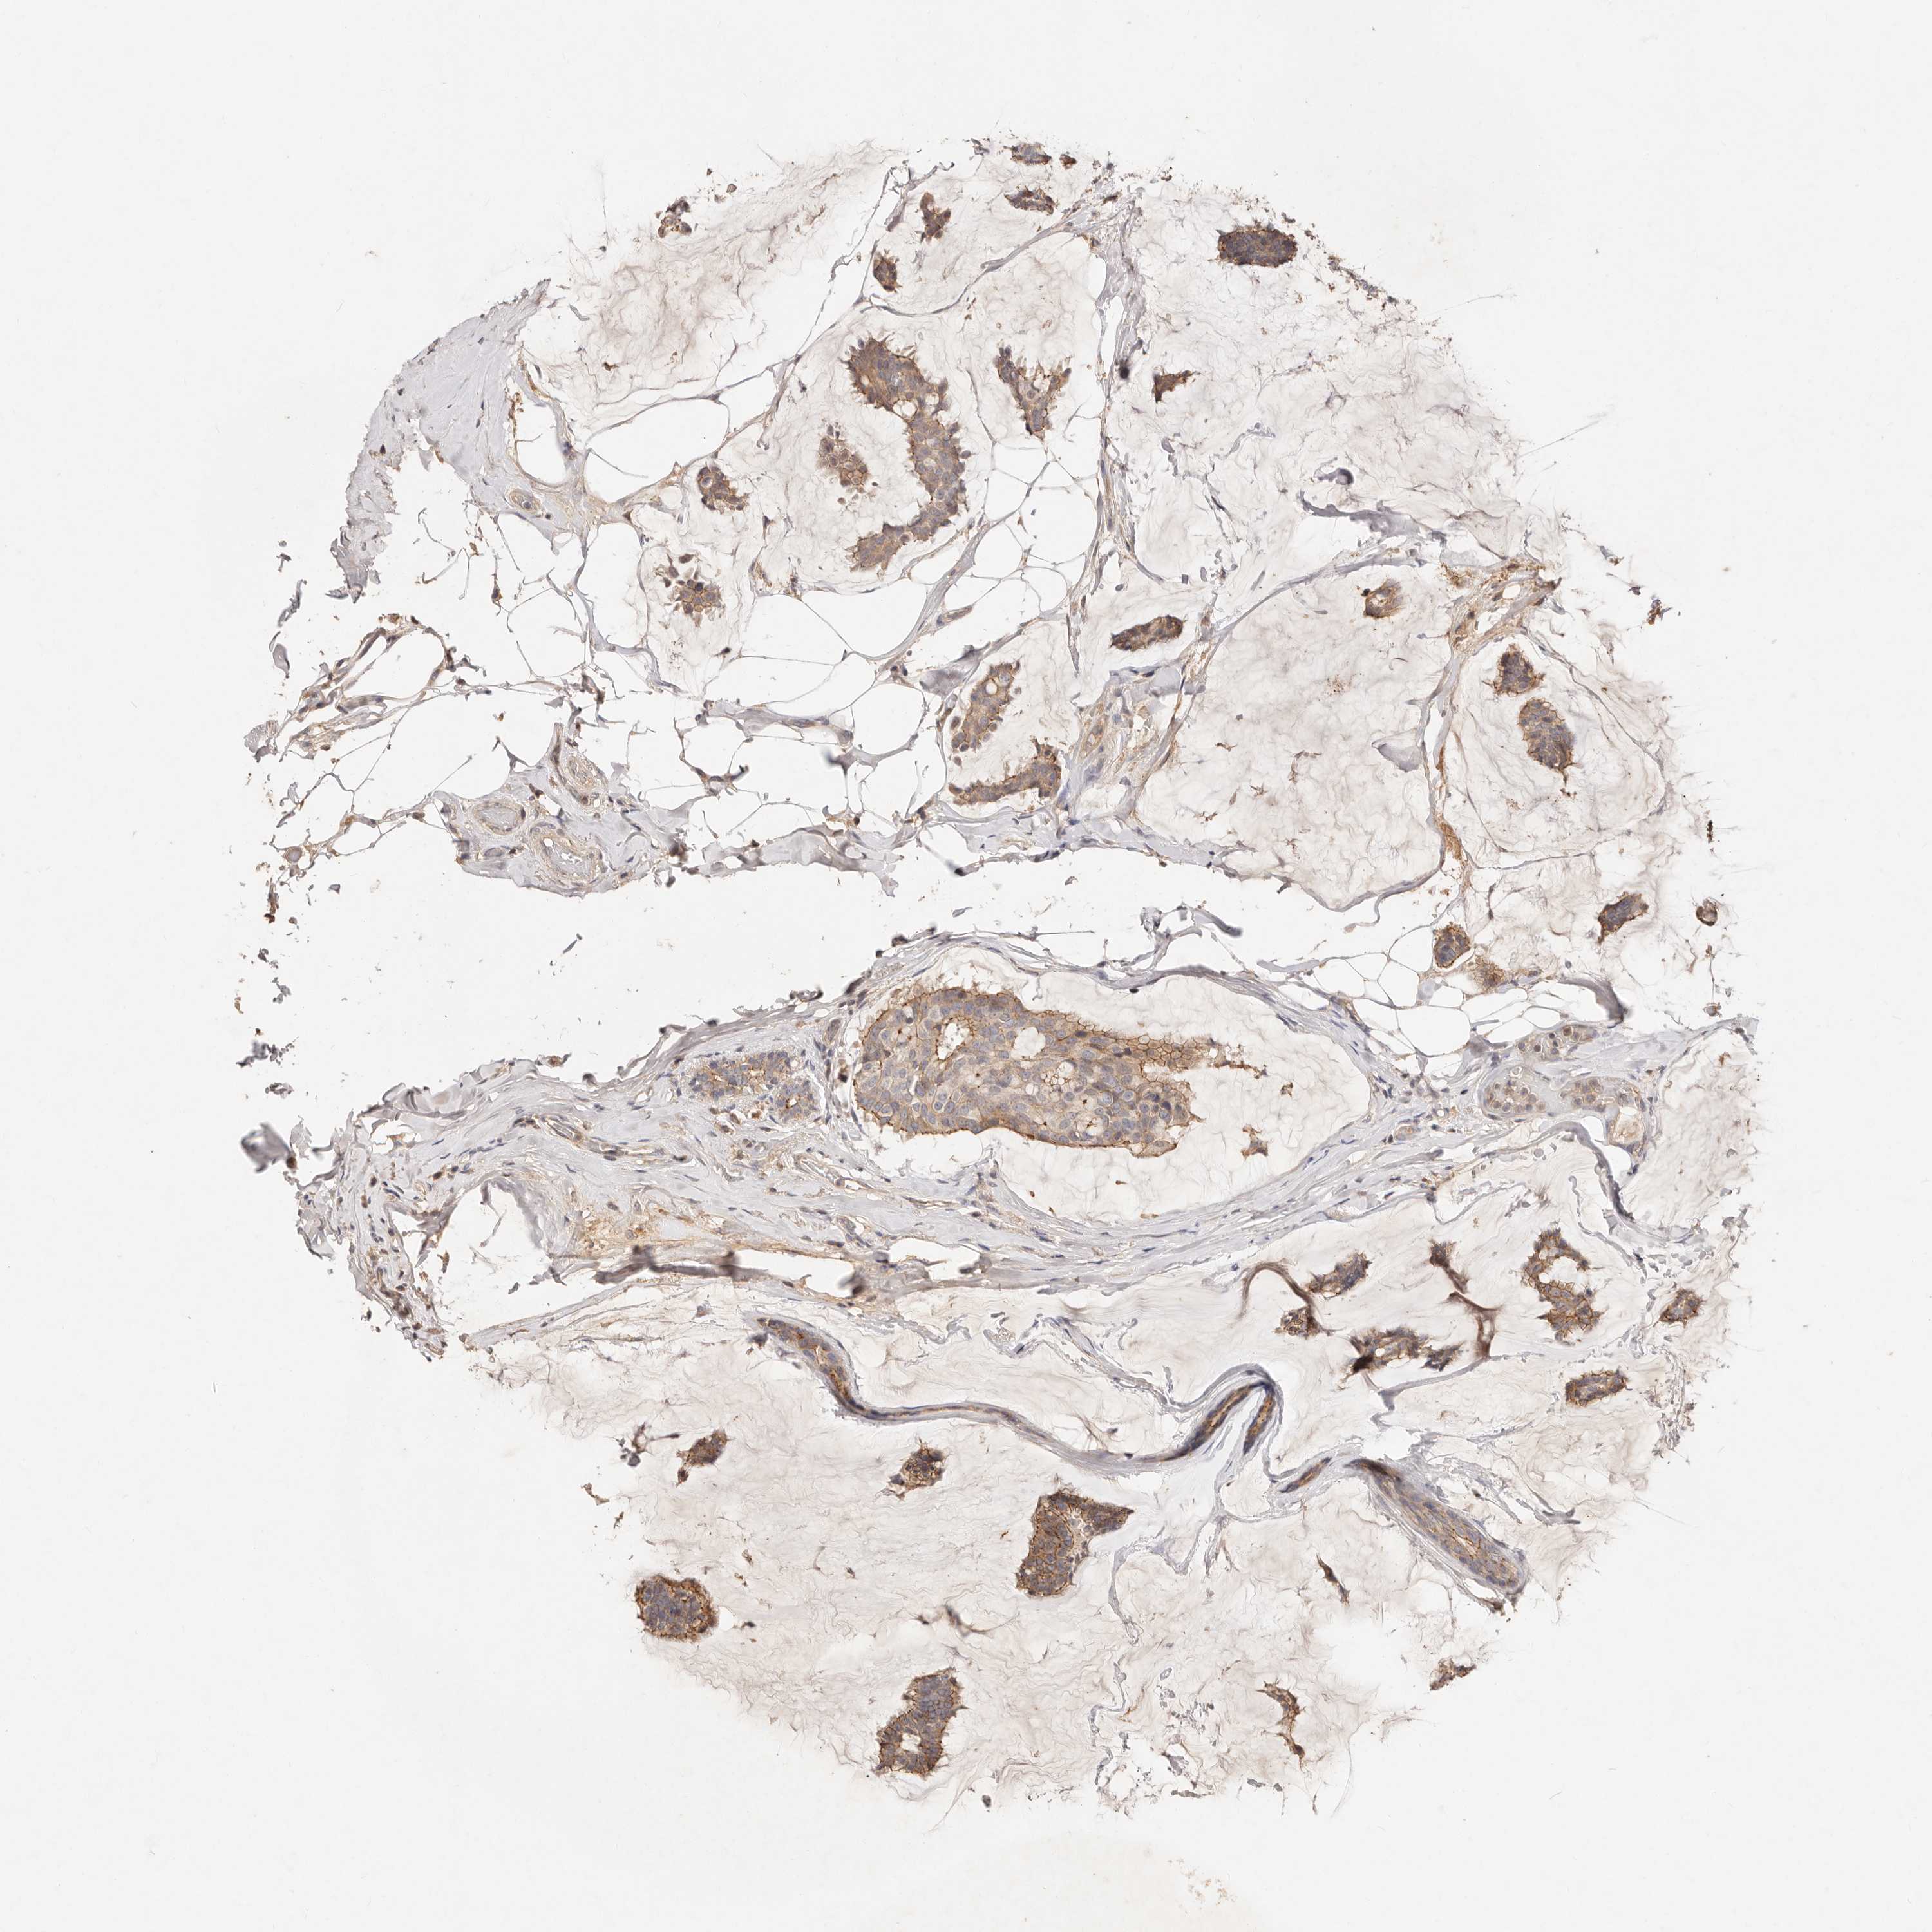

CANCER BREAST CANCER Show tissue menu

BRCA TCGA BRCA VALIDATION PROTEIN EXPRESSION

ANTIBODIES

AND

VALIDATION